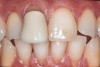

3. Excessive Shear and Tensile Stress Risk Assessment

Figure 3  Image demonstrating deep overbite in which shear and tensile stresses would be at least medium. Bonded porcelain would require maintenance of enamel and an occlusal strategy to reduce leverage on the teeth.

Figure 3